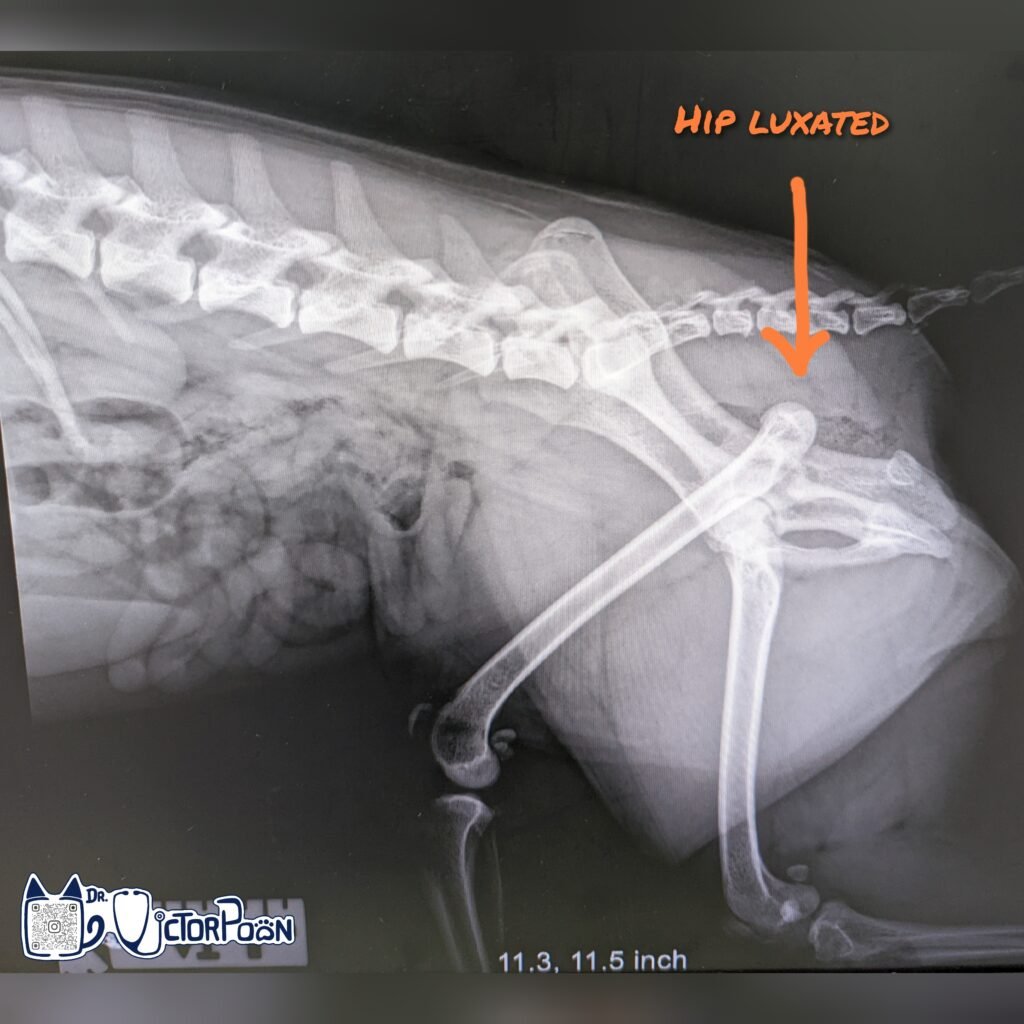

The most common cause of hip luxation is trauma and some of these patients have underlying hip dysplasia which predispose them to luxation with less severe trauma. The femoral head is usually dislocated dorsal to the acetabular rim, with a craniodorsal (front and up) position being the most common. It is essential to confirm hip luxation orientation by X-ray because the treatment plan is different. Closed reduction should be attempt for acute, uncomplicated hip luxation (normal looking acetabular rim and femoral head)